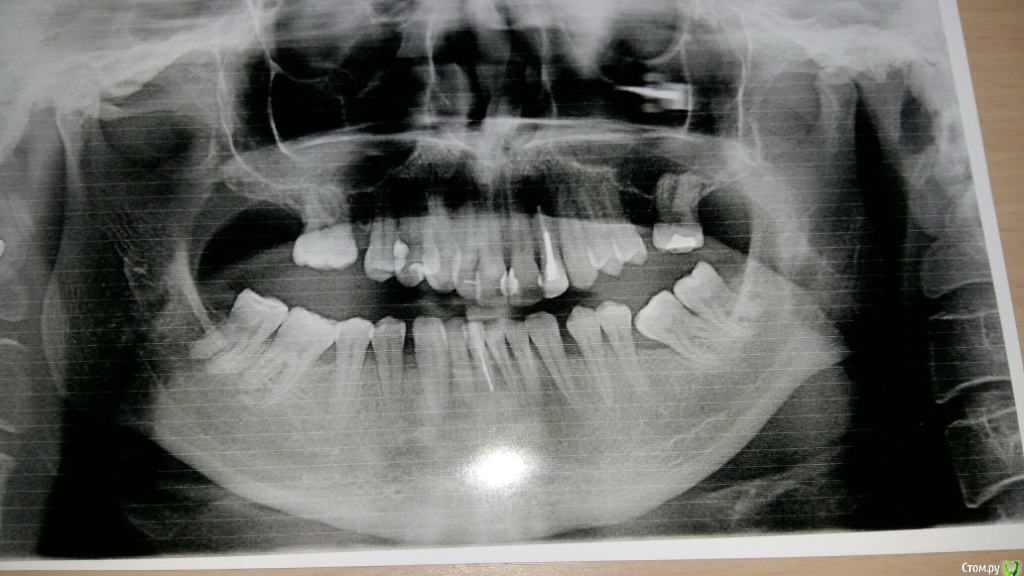

VVQW Опубликовано 6 декабря, 2016 Поделиться Опубликовано 6 декабря, 2016 В результате некачественной ортодонтии более 10 лет назад имеется такая картина. Посоветуйте что-можно сделать?Верхние 6-ки удалены перед брекет системой, по решению ортодонта. Верхние 8-ки не выросли, нижние 6-ки - удалены в подростковом возрасте до 14 лет. http://s019.radikal.ru/i639/1612/56/1345f17db908.jpg http://s019.radikal.ru/i630/1612/55/145ef7c813b2.jpg http://s017.radikal.ru/i440/1612/c2/74bd4da2643e.jpg http://s008.radikal.ru/i303/1612/b4/e80683ed7d2b.jpg http://s010.radikal.ru/i314/1612/74/6d2f9671b0d5.jpg http://s018.radikal.ru/i502/1612/97/9a15fcf4ddd3.jpg http://s020.radikal.ru/i715/1612/59/9bb4a006621f.jpg Ссылка на комментарий

VVQW Опубликовано 6 декабря, 2016 Автор Поделиться Опубликовано 6 декабря, 2016 Добрый день. Беспокоят клиновидки и их прогрессирование из-за неправильной окклюзии.Которая из-за неккоректно проведенного ортодонтическлго лечения. Одно из мнений ортодонтов, 50/50, что надо провести повторное лечение и восстановить зубной ряд имплантами. Вот только дальше варианты у всех свои. Если в верху подвинуть 7 к 5, есть место для импланта? Кость позволит? И наоборот если сделать место под 6, можно ли туда импоант поставить? Спасибо. Ссылка на комментарий